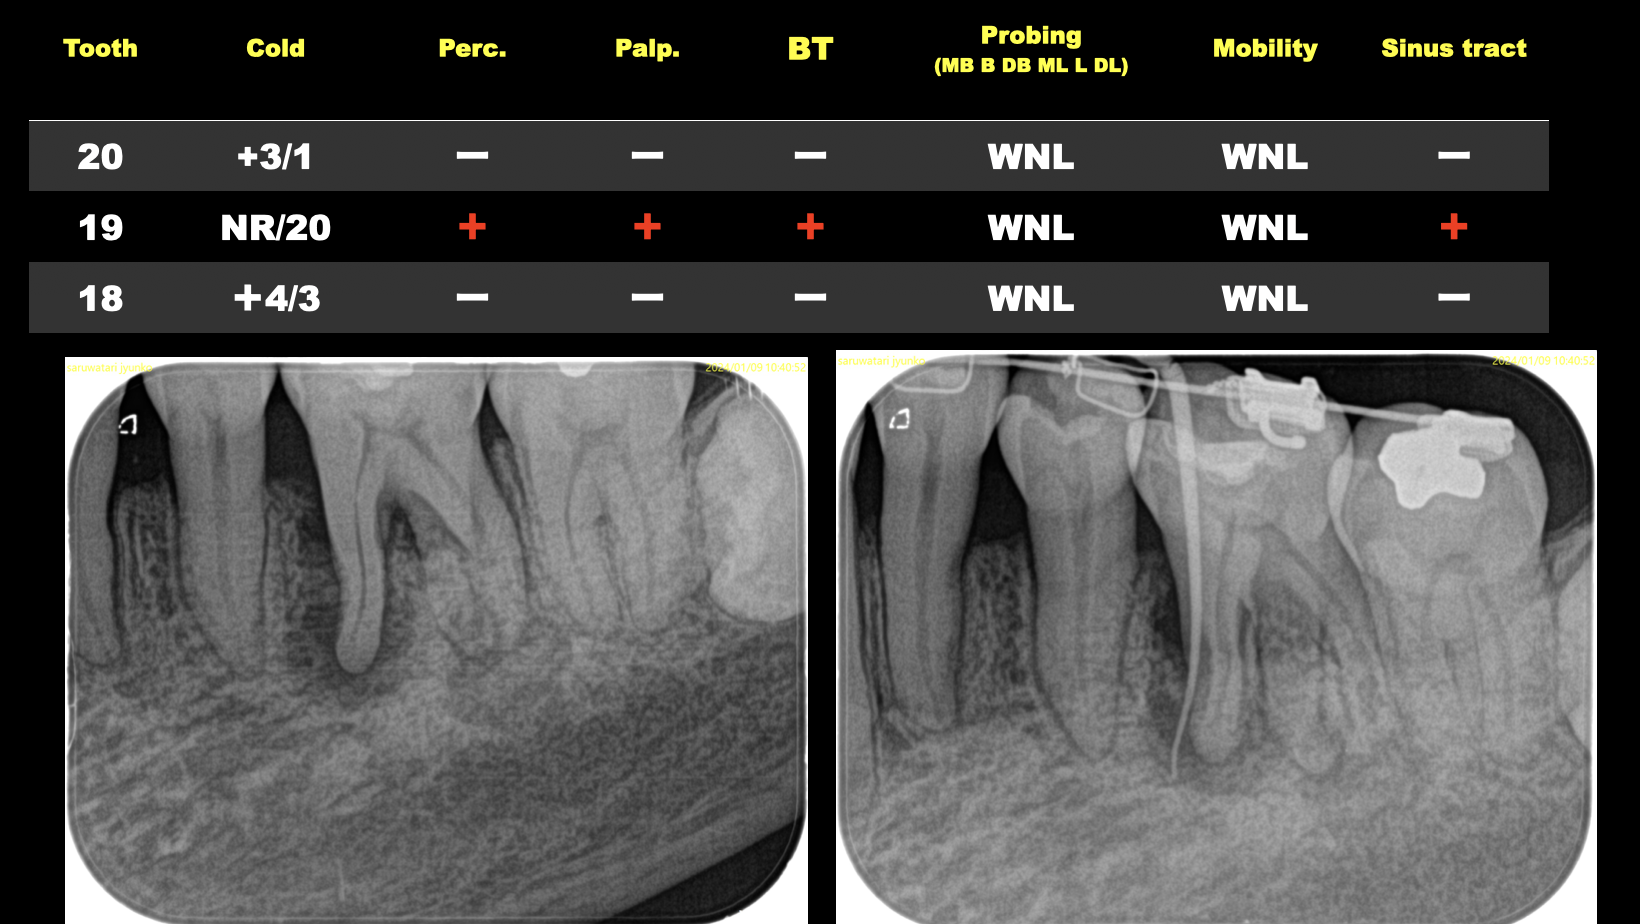

そして最後にケースを提示した。